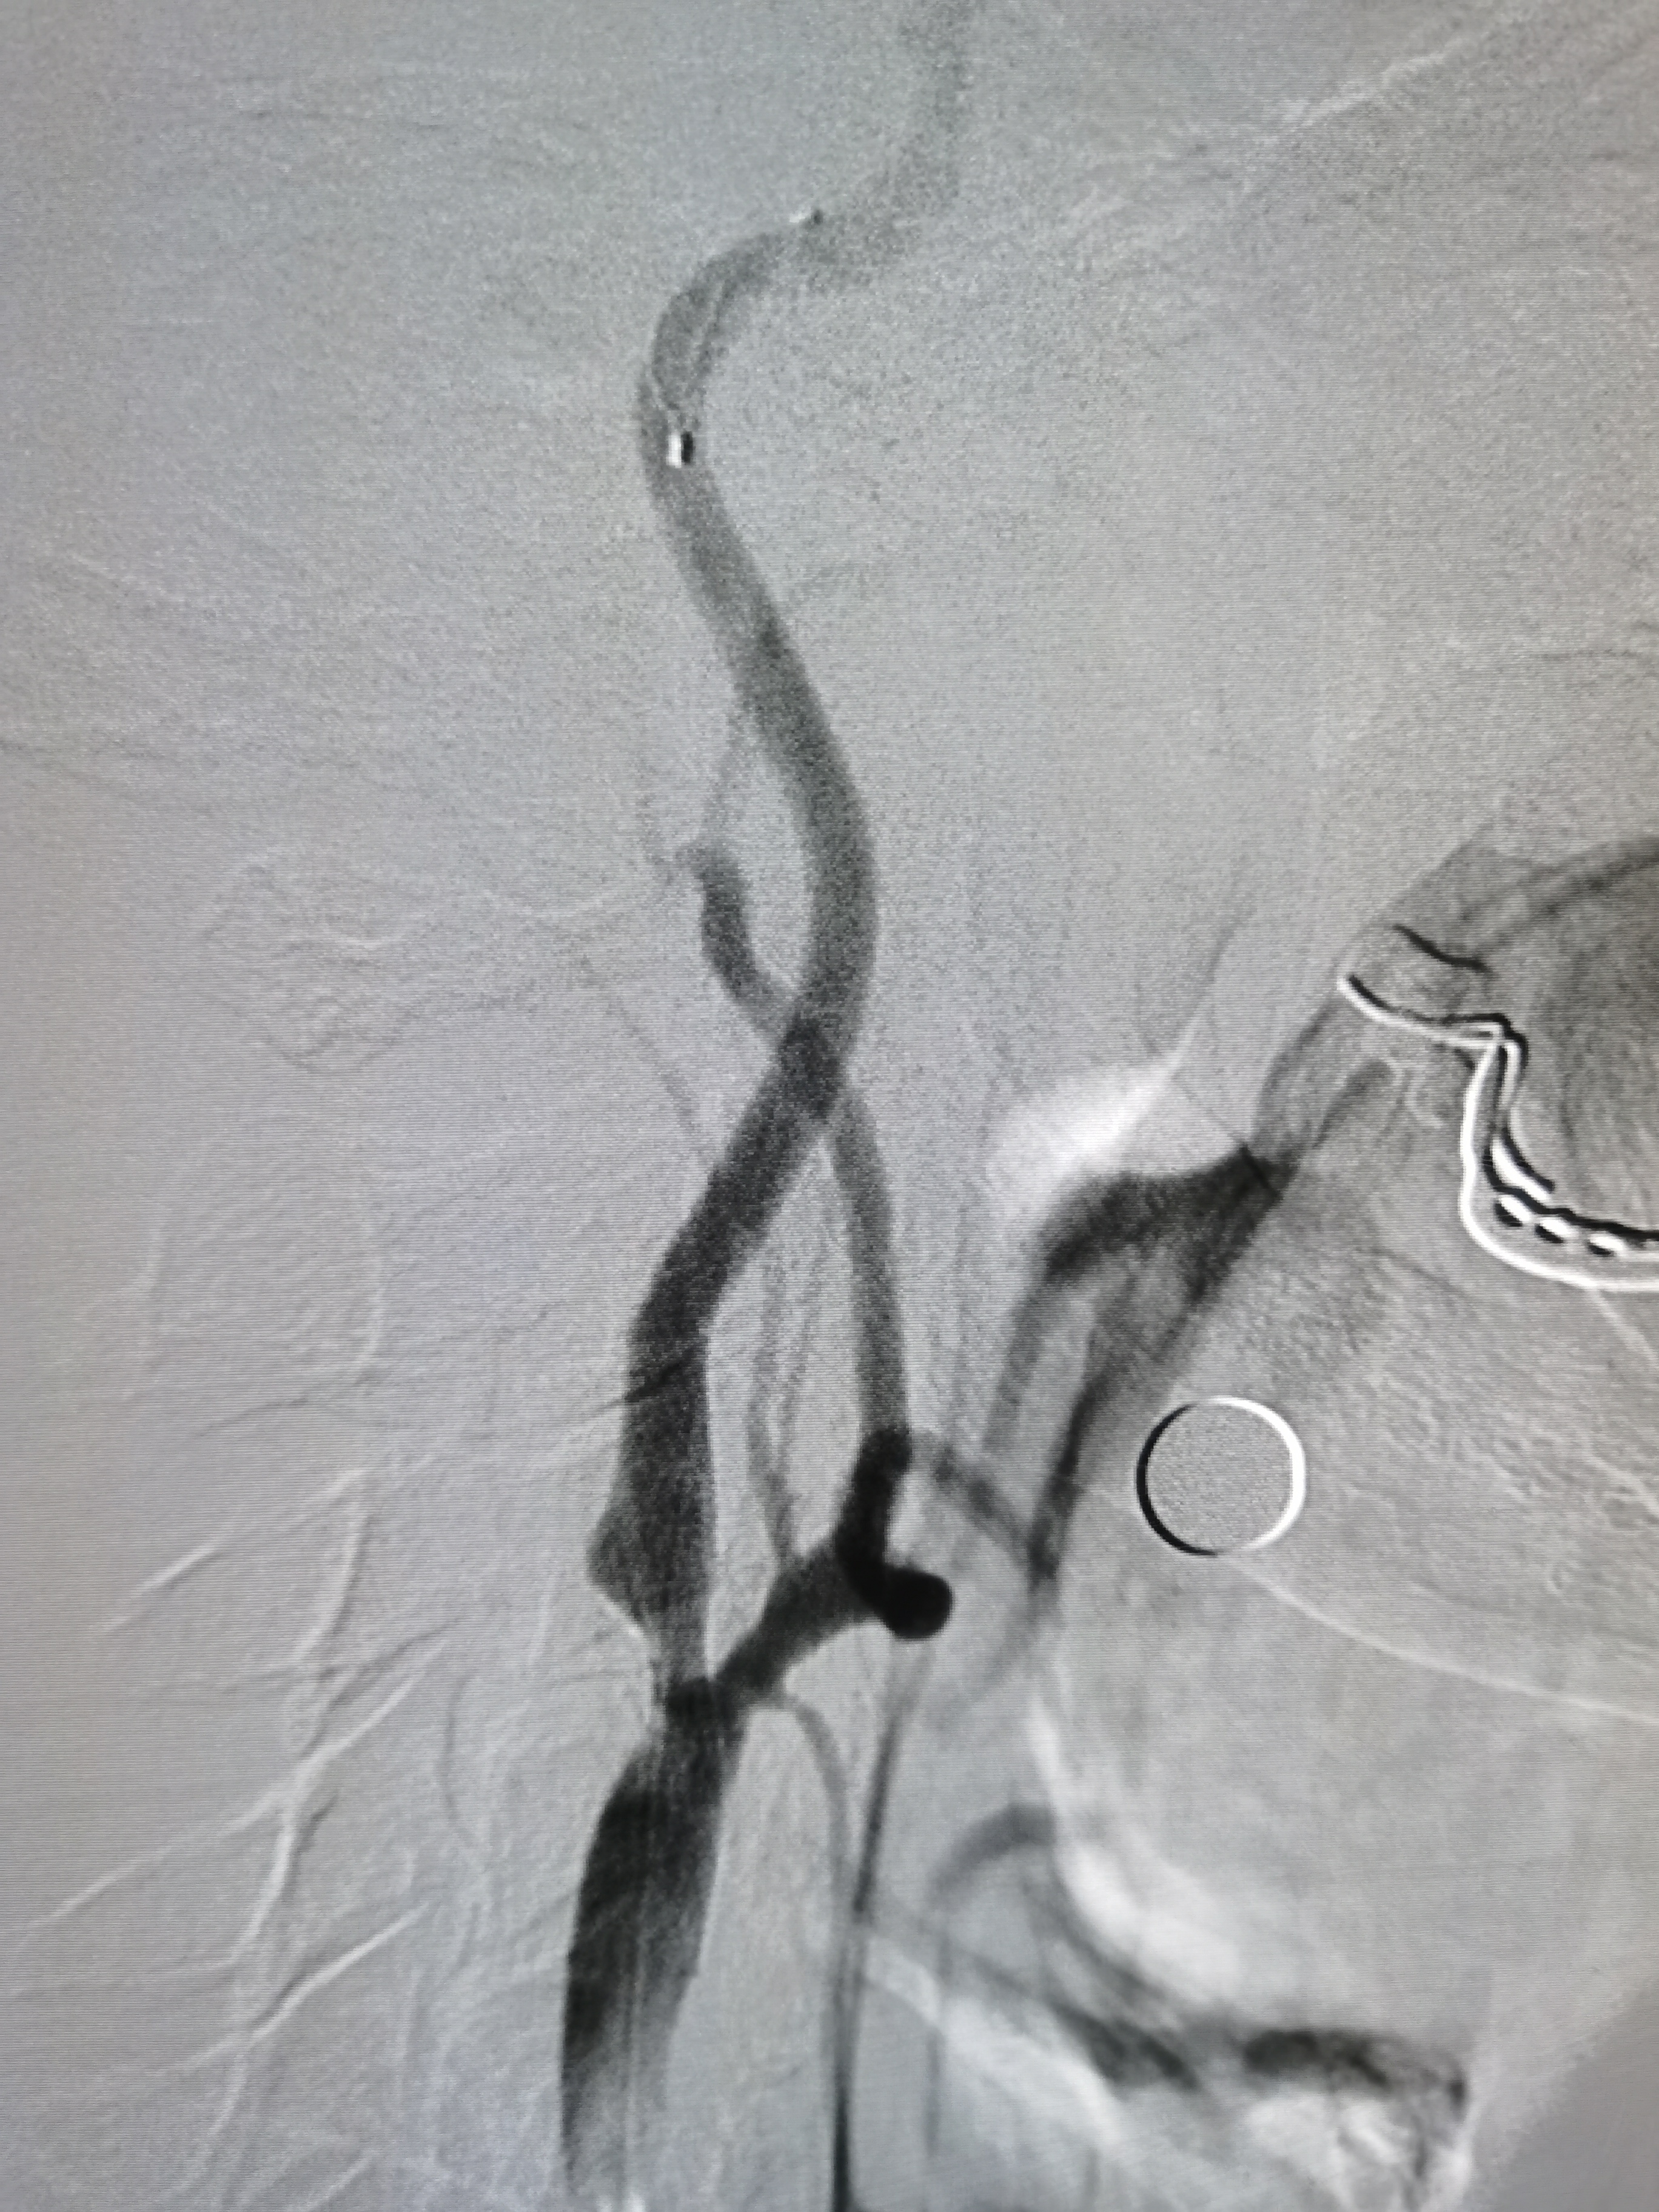

将导引导管调至右侧颈总末端,送入远端保护伞,4/30球囊预扩。

7-9/40支架定位

支架释放后狭窄改善,考虑患者高龄,颅内动脉硬化,担心术后高灌注出血,遂未再进行大球囊后扩。

撤出保护伞,造影见狭窄改善明显。

术前术后对比